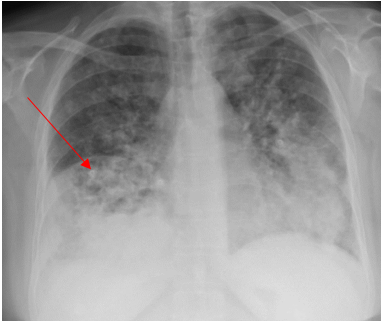

She was diagnosed with presumed community-acquired pneumonia, prescribed doxycycline 100 mg orally twice daily for ten days along with ibuprofen and discharged home to follow up with her primary care physician. However, the chest pain did not get better, and she presented again to the emergency room a week later, reporting unresolved chest pain in addition to new development of fatigue, shortness of breath, cough and intermittent fever with a maximum recorded temperature of 102°F (38.8°C) that has been measured at home. Upon her second presentation to the emergency department, her vital signs revealed a temperature of 98.9°F (37.2°C), blood pressure of 120/70 mmHg, Pulse of 99 per minute, and respiration of 16 per minute, and Oxygen saturation 99% on room air. Moreover, her repeat Chest -X-ray showed dense airspace opacity in the right middle lobe, while repeat CT Chest angiography did not reveal any evidence of pulmonary embolism. There was a consolidation in the right middle lobe and a smaller amount of infiltrate in the right lower lobe and right upper lobe but no pleural effusion. There was a calcified granuloma on the left lung and mediastinal lymphadenopathy with the largest mediastinal lymph node in the subcarinal region measuring 1.8 cm and 1.7 cm right hilar lymph node thought to be reactive to the pneumonic process. Laboratory testing was significant for leukocytosis with (WBC) 20.2 K/UL. She was discharged home again on oral Levofloxacin tablet 750 mg once daily for five days, oral prednisone tapering doses, along with ibuprofen and acetaminophen to follow up with her primary care physician. The patient came back again two days later to the emergency department with current presentation with persistent and unresolved right-sided chest pain located behind the shoulder blade and upper right chest and worsening respiratory symptoms, including dry cough, shortness of breath, subjective fever, chills and weight loss. The chest pain seems to get worse with deep inspiration while she lays flat and improves while sitting up. Her medications included Albuterol metered dose inhaler, atorvastatin, metoprolol, omeprazole, and levofloxacin. Physical examination was noteworthy for an ill-appearing person in mild respiratory distress with tachypnea and tachycardia. Her vitals included: temperature of 99°F (37.2°C), Respiration of 18 per minute, Pulse 99 beats per minute, blood pressure of 125/61 mmHg, Oxygen Saturation of 92%-94% on room air. The chest exam demonstrated diminished breath sounds at the right lung base with right lower chest scattered crackles and mild anterior and posterior right-sided chest wall tenderness. Also, there were no skin lesions observed.

Laboratory testing was notable for elevated WBC, 19.5 (4.0-10.5 K/UL), neutrophils 78.3%, lymphocytes 7.7%, Monocytes 13.5%, eosinophils 0.2%, basophils 0.3%, Procalcitonin 1.46 ng/ml (reference range :< 0.25 ng/ml), SARS-COV 2 was negative. Blood culture, sputum culture, urine strep and legionella urine Antigens were negative, and the upper respiratory PCR panel was negative. MRSA PCR negative. Chest-X ray revealed a consolidation within the right lower lung field, while the CT Chest Angiography showed no evidence of acute pulmonary embolus. Furthermore, there was a progression of consolidative changes in the right middle lobe, traces of right pleural effusion, mild bilateral lower lobe atelectasis, and rounded opacity in the posterior left lower lobe measuring 10 mm. On the same note, there was rounded opacity in the right lower lobe measuring 13 mm, which was a new finding from the prior imaging study, and prominent mediastinal and hilar lymph nodes with the right paratracheal lymph node measuring 13 mm and right hilar lymph node measuring 19 mm (Figure 3 and 4).

Figure 3. Portable Chest X-ray on Hospital admission showing consolidation in the right lower lung field.